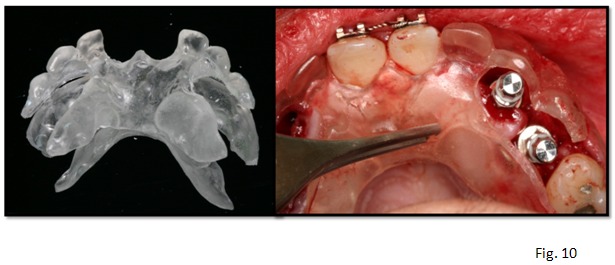

Habitualmente este tipo de férulas quirúrgicas se realizan con una resina transparente, lo que facilitará visualmente al cirujano colocar los implantes en la correcta posición (Fig. 10).Si también va a ser una férula radiológica deberá tener material radiopaco a nivel dentario.

La preparación de la férula puede ser en el laboratorio dental, o en clínica. Las ventajas de hacerlo en clínica son el ahorro de tiempo y costes.

Antes de que el material acrílico fragüe se cerrará el duplicador totalmente y se esperará al fraguado total. Pasado el tiempo necesario abrir el duplicador, obteniendo de esta forma la guía quirúrgica deseada, y se procederá a recortar los excesos con una pieza de mano, realizándose cuantas perforaciones sean necesarias como guía para la ubicación de los implantes.(Fig. 11)